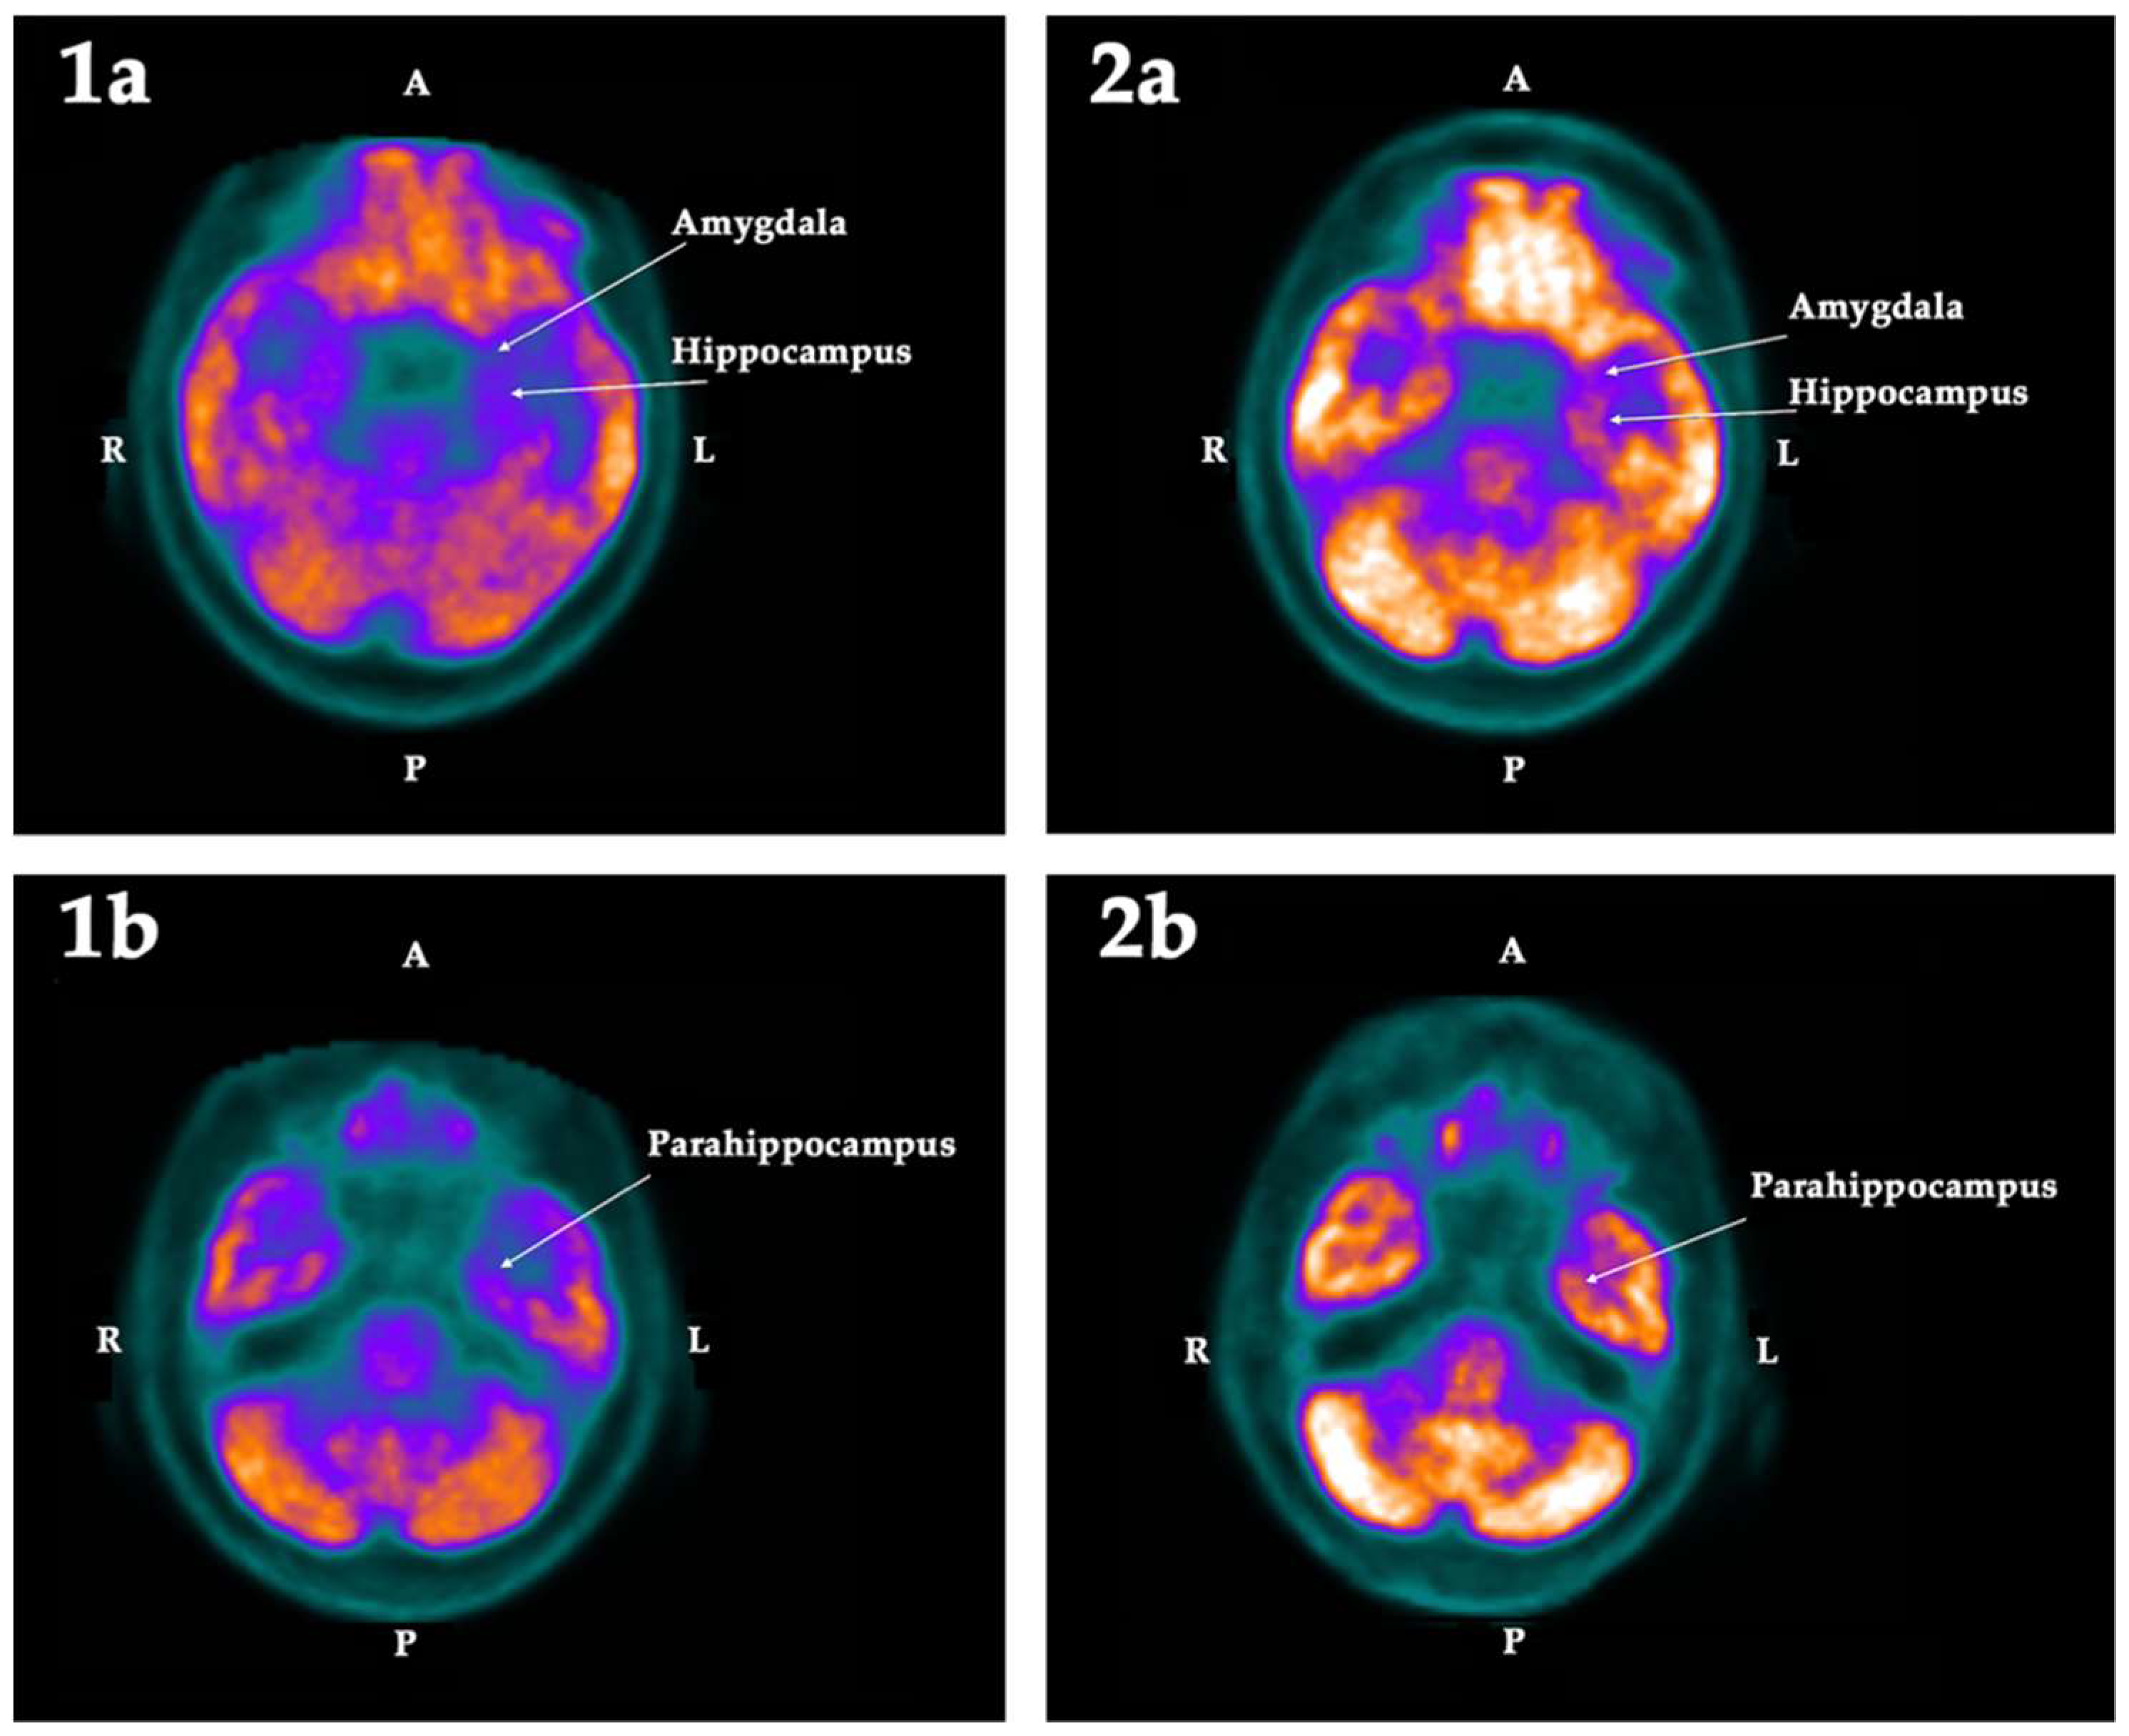

2.2. PET-SCAN Studies

| ROI | First PET-SCAN | p < | Second PET-SCAN | ||||||

|---|---|---|---|---|---|---|---|---|---|

| L | R | Asym | Hypom | L | R | Asym | Hypom | ||

| Hippocampus | −12.49 | −6.55 | −5.94 | Left | 0.025 | −6.49 | −2.84 | −3.65 | |

| Amygdala | −13.38 | −7.20 | −6.18 | Left | 0.025 | −9.47 | −1.52 | −7.96 | |

| Parahippocampus | −11.93 | −7.24 | −4.69 | Left | 0.025 | −10.86 | −8.19 | −2.67 | Bilat |